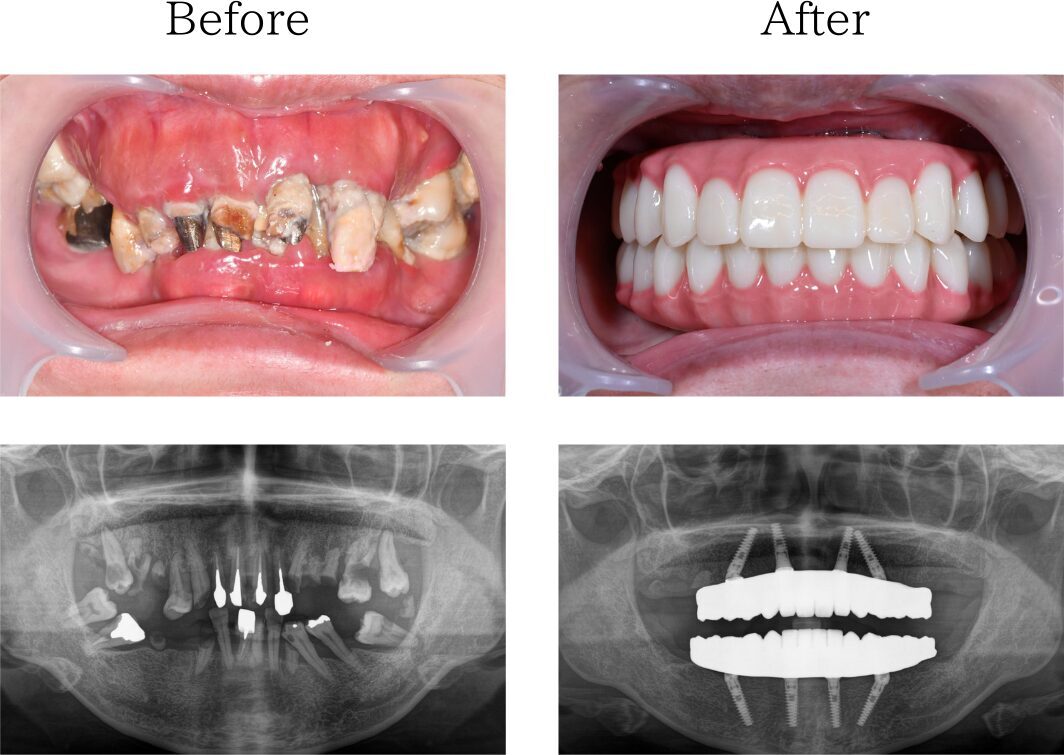

歯がボロボロ

歯科医院にインプラントを相談しても「骨が全くない」「入れ歯しか無理」「オーバーデンチャー」と言われた患者さんのレントゲン画像です。骨は全くありません。

オールオン4ザイゴマインプラント

日本全国に電話して探して、やっと当院にたどり着いた患者さんもいれば、歯科関係のご友人の紹介でいらっしゃった方もいます。ザイゴマインプラントだけで完成させるオールオン4はあなたの悩みを解決します。

3kiritori

※治療内容:上下顎オールオン4ザイゴマ4本

※費用:4,795,000円*モニター価格

※期間:半年

※リスク:出血、痛み、腫れ、しびれ

「他院のインプラント治療に不信感」

70代 男性 (福岡) の場合

他院で入れたインプラントは一年くらいで悪くなり抜きました。その後他のインプラントも揺れ始め、その歯科医院に不信感を抱くようになり、最善の治療はないかとネットで調べていたところ、おおたわ歯科医院を見つけました。YouTubeやブログを読んでいて、大多和先生になら任せられると思い相談し、オールオン4の手術を決めました。